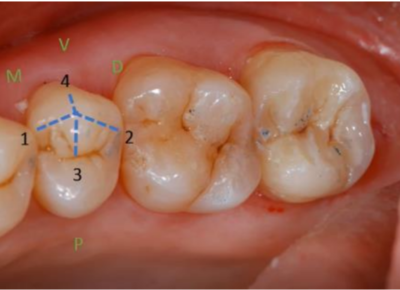

Et la crêtes cuspidienne vestibulo-lingual tu vois bien sur la photo que ça vient sur ta dent et que ça la sépare en arête vestibulaire et en arête occlusale

crêtes.png

crêtes.png (45.86 Kio) Vu 797 fois

Bonjouur je relance le sujet désolée, mais je ne comprends pas pourquoi on dit que les crêtes vestibulo-palatines/linguales sont composées d'une arête vestibulaire et d'une arête occlusale??

Sur la ligne rouge de la photo je comprends plutôt que la crête passe sur 2 arêtes occlusales de 2 cuspides différentes.

Quand on regarde sur la photo qui nous montre les différentes arêtes il me semble que la ligne rouge (=crête v-p/l) ne passe pas par la "4" qui correspond à l'arête vestibulaire... mais par contre qu'elle continue sur la cuspide linguale au niveau de sa face occlusale

Est-ce que du coup c'est pas maxi précis sur la photo et qu'une crête vestibulo-linguale passe par 2 arêtes occlusales + 1 vestibulaire + 1 linguale et que l'on raccourci à 1 arête vestibulaire + 1 arête occlusale (par cuspide du coup) ?? mais dans ce cas est-ce que l'on peut dire qu'elle est formée d'une arête occlusale + 1 arête linguale (si on considère une cuspide linguale)